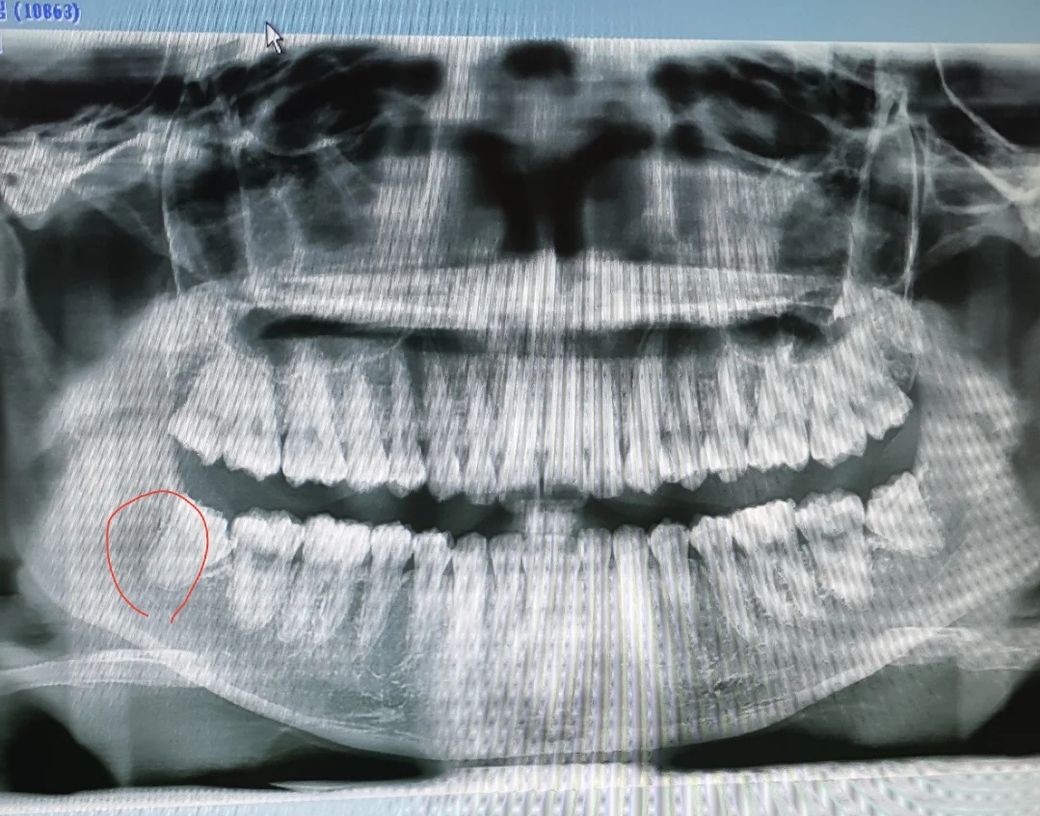

상악사랑니 발치시 마취주사 아픈가요?

현재 왼쪽 하악사랑니는 뽑아서 상악 2개,

하악 오른쪽 매복 하나 남았습니다.

상악 사랑니가 지금 아프진않은데 그냥 뽑고 싶어서요.. 근데 찾아보니 상악은 입천장에 마취하는데 더 아프다고 하더라구요. ㅠㅠ

• 하악 마취할땐 하나도 안아팠는데 입천장 마취는 많이 아픈가요?

• 뽑는김에 상악두개 하악 매복사랑니 동시에 뽑고 싶은데 가능한가요?

• 1번 째 사진